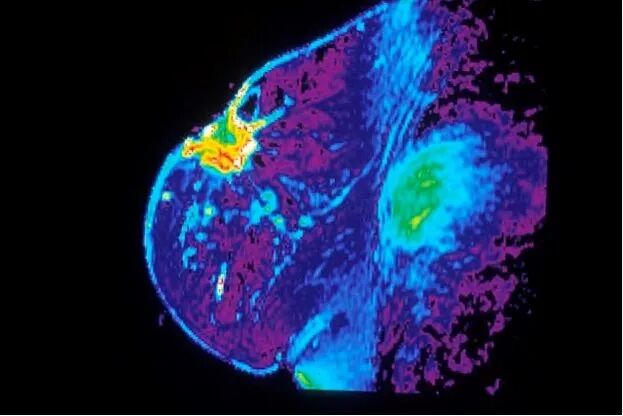

乳房MRI。图源:Public Domain - National Cancer Institute